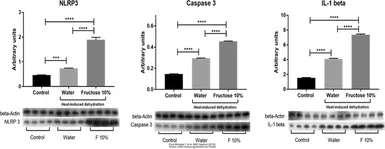

The data was published in the 2020 in Antioxidants (Basel). PMID: 33203103

The data was published in the 2020 in Antioxidants (Basel). PMID: 33203103